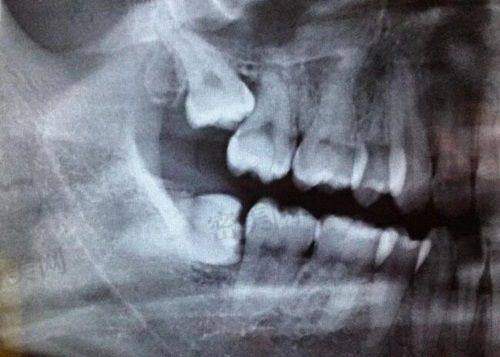

种植牙是特别多中老年伙伴关心的大事,瑞和提供免费术前CT拍片评估,制定专属种植方案,让过程更加安心。